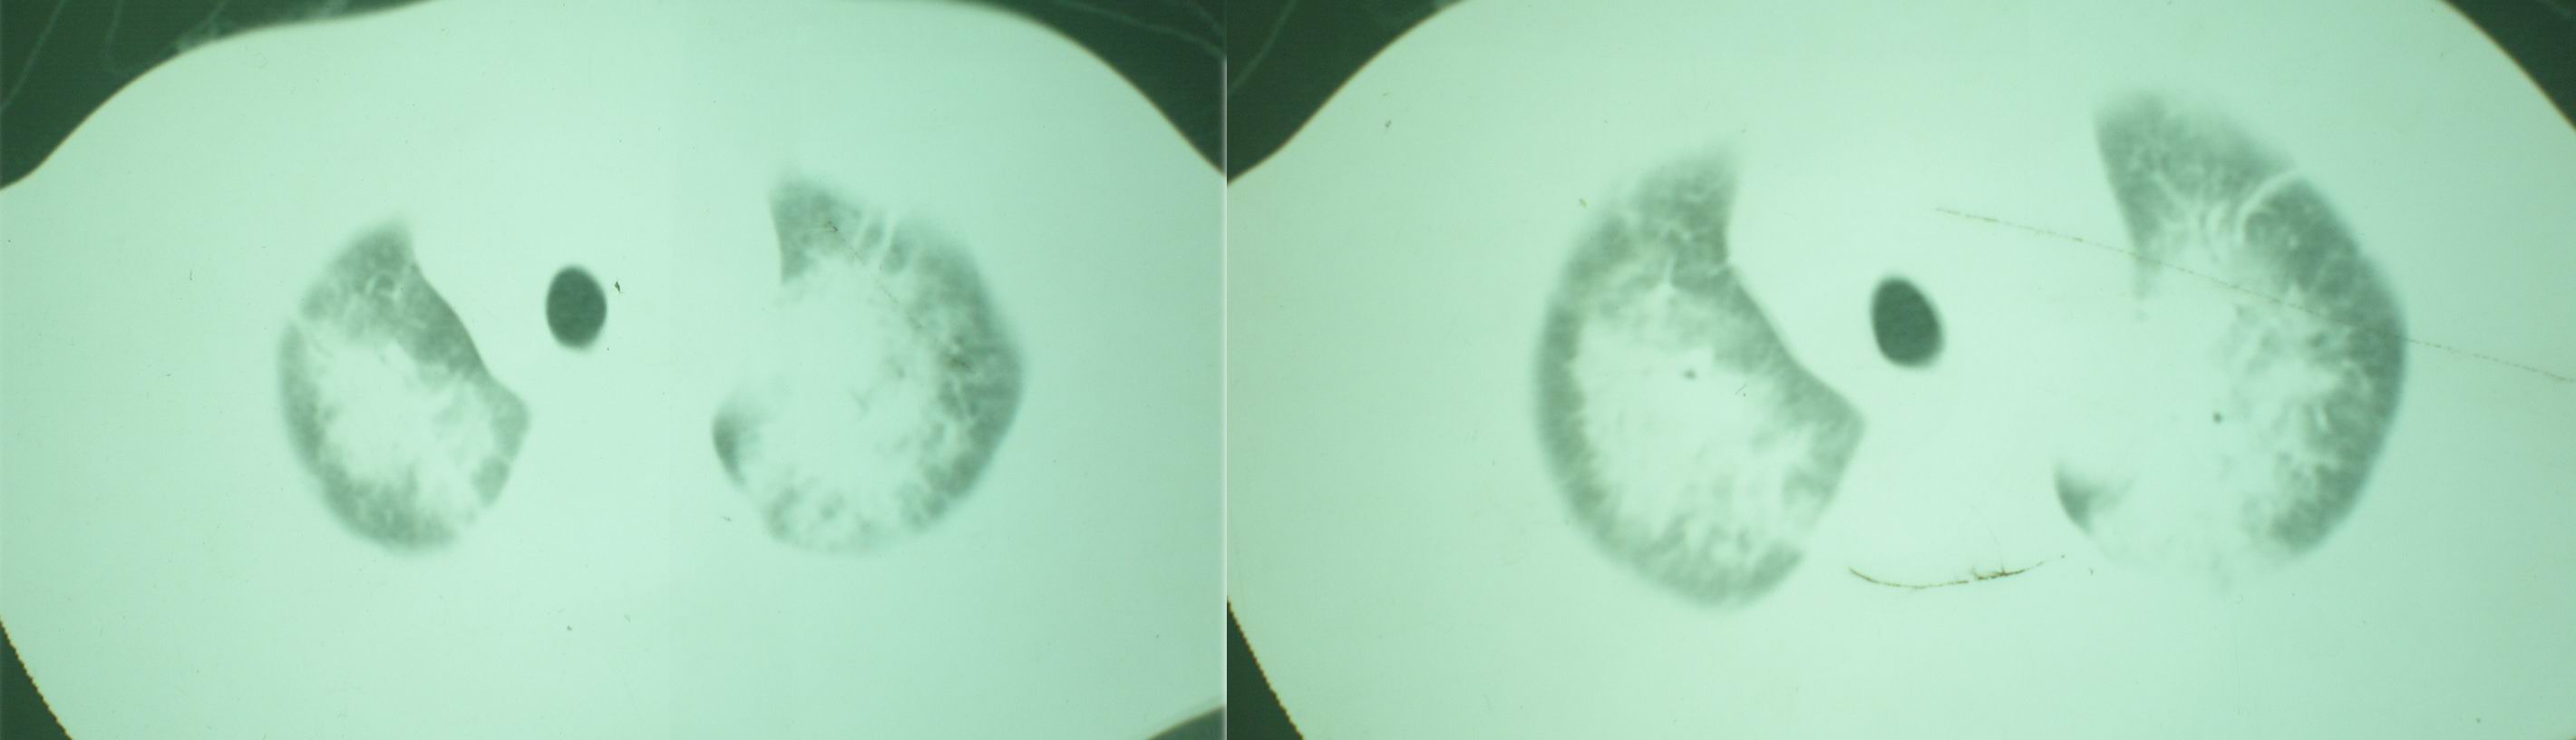

病人资料:男,52岁,因体癣股癣等皮肤病行激素治疗,因突然大剂量减药而起病,病情危急,9月8日曾在上级医院住院治疗,9月18日复查了ct片,相关检查及住院小结以图片资料上传。

2008年9月18日ct片

[face=宋体]显然上级医院进行了抗结核,抗真菌,抗炎等治疗,目前病人肺内病灶基本消失,双侧胸腔积液,右侧积液量有吸收,抗结核一个多月,现在病人疑问,结核的诊断是否有疑义,抗结核是否继续,因为那个毕竟副作用大。[/face]

我仔细看了下病人的出院小结,当时情况危急,诊断里有1型呼衰。心包周围的是脂肪密度。结合三次ct扫描的图象分析,个人认为:1、病人目前肺部病灶基本消失,双侧胸腔内少量积液,抗结核治疗才一个多月,就算是结核,抗结核治疗有效果,为何效果如此好,一点纤维灶的痕迹都没有呢,再就是患者做过气管镜检查及活检、痰检均未找到结核的证据。所以不支持结核的诊断。

2、结合现在的ct片,考虑:肺水肿及真菌感染,双侧胸腔积液。